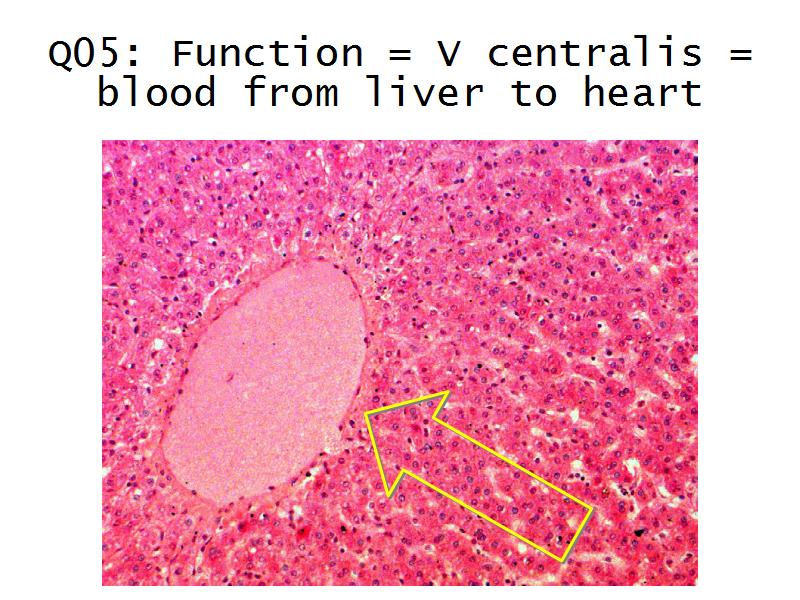

- The renal corpuscle